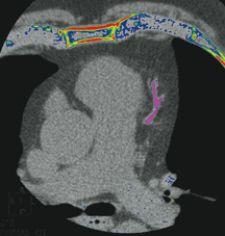

Barco has received 510(k) premarket clearance from the FDA for CARDIAMETRIX, a suite for structural and functional analysis of contrast-enhanced cardiac studies. It is available with the company’s software suite for advanced visualization and analysis VOXAR 3D.

The VOXAR 3D CARDIAMETRIX suite has many features including integrated clinical applications for coronary artery vessel analysis, calcium scoring, 4-D cardiac analysis and left ventricular functional analysis. The suite assesses multiphase studies using up to six phases to present 2-D, 3-D and 4-D images of the heart.